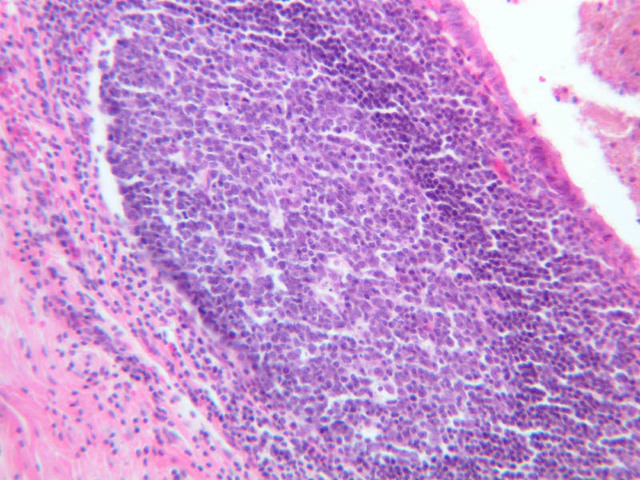

In the section of appendix (slide B-20, H&E [2.5x, 10x, 20x, 40x] [2.5x, 10x, 20x, 40x]), you will find that lymphatic tissue, which is distributed both diffusely and as nodules, distorts the crypts of Lieberk\xFChn and also blurs the usual features of the mucosa and submucosa. Nonetheless, you should be able to find recognizable profiles of intestinal glands as well as slips of the muscularis mucosae among the lymphoid elements. Note that in the appendix there are no absorptive cells and no villi.